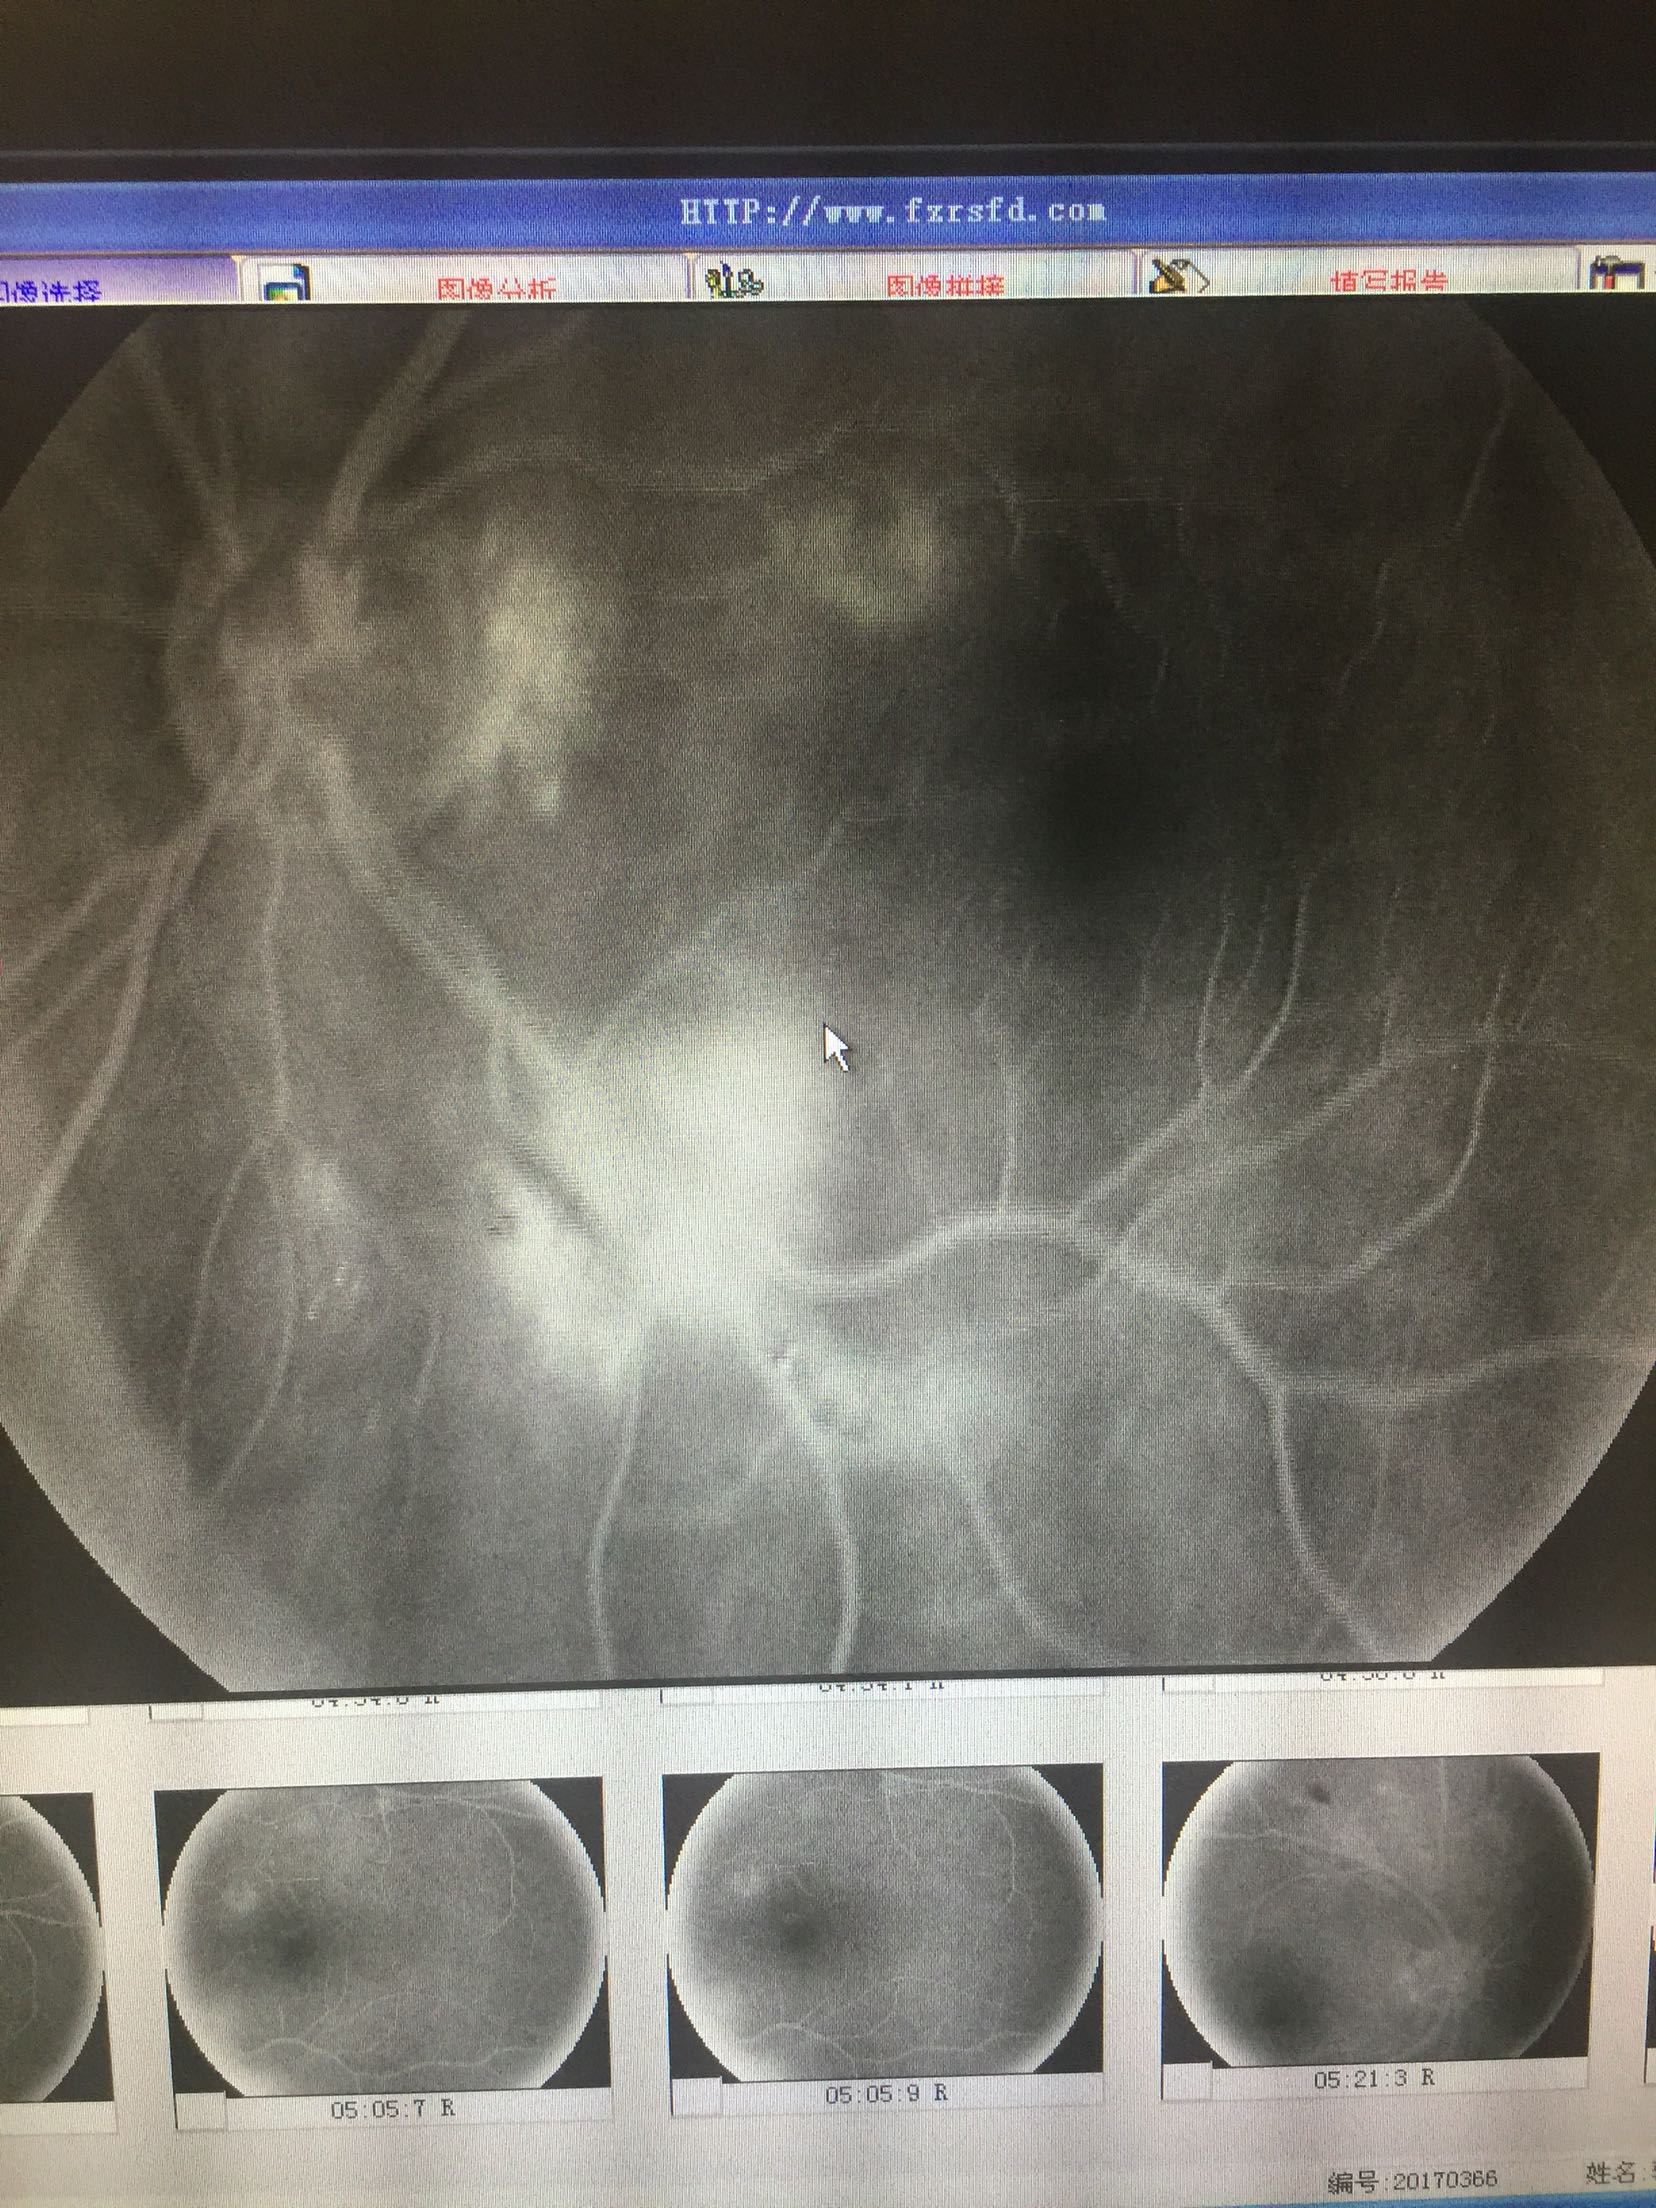

视力: 右眼0.6 左眼0.5 双眼睑无水肿,结膜无充血,角膜透明,前房正常,瞳孔圆,对光反射可,虹膜纹理清,晶体轻度浑浊,眼底视盘界清色可,黄斑区中心凹反光还可,网膜散在片状出血及硬性渗出 眼压:13/17 血压100/70mmhg 随机血糖:6.2

心电图:窦性心律,67次/分 造影:左眼动脉充盈时间为23秒,静脉充盈时间为27.2秒,双眼全视网膜可见片状荧光遮蔽及黄白色硬性渗出,早期双眼全视网膜散在点状高荧光,晚期有荧光渗漏

双眼糖尿病视网膜病变 药物促进血液吸收,改善眼底循环,视网膜光凝治疗